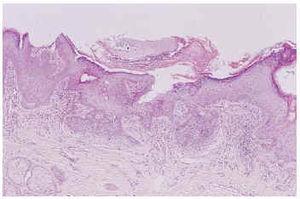

Fig. 2.--Nevo sebáceo asociado a tricoblastoma.